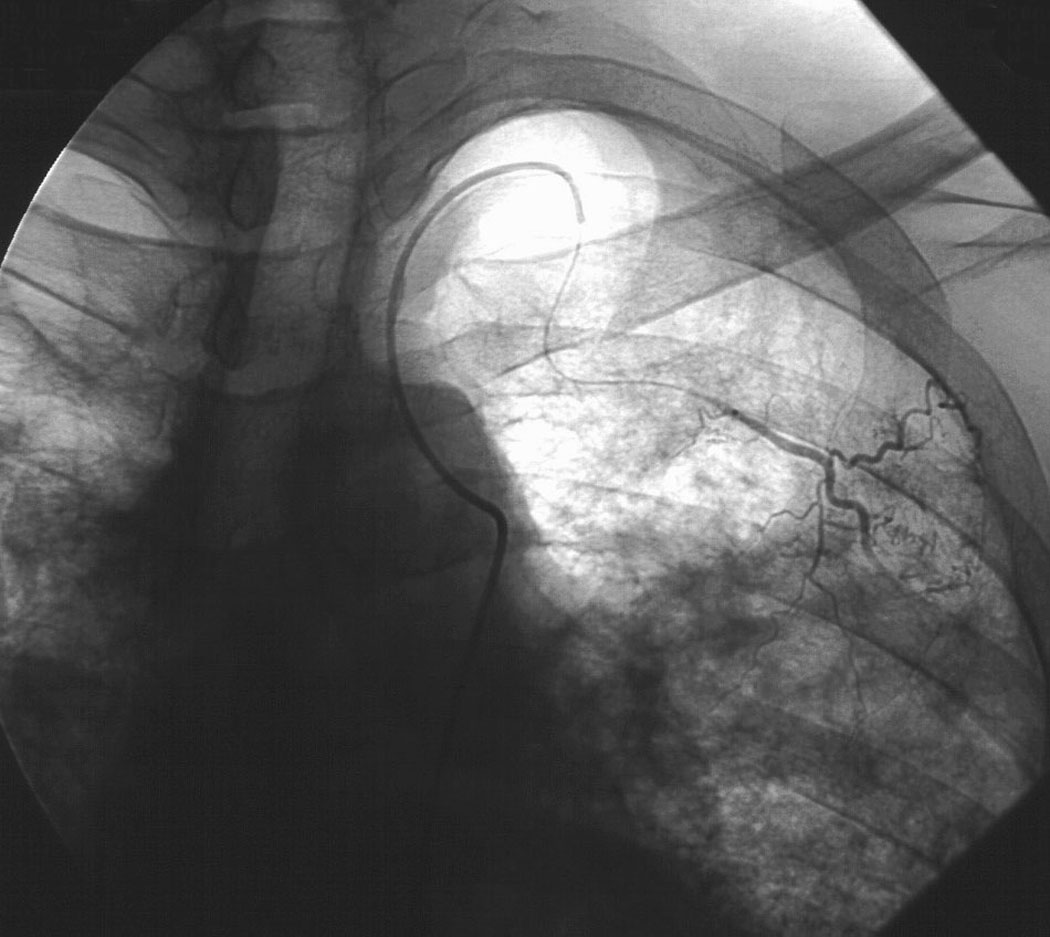

The definitive treatment of symptomatic aspergilloma is surgical resection. Patients with aspergilloma who present with hemoptysis are at risk of death due to massive hemoptysis and/or respiratory insufficiency caused by aspirated blood. Catheter embolization of bronchial arteries can be used to control acute bleeding (Figure 1), but is not durable. Likewise, intracavitary instillation of antifungal agents has mixed outcomes and seldom results in complete resolution of the cavity (Figure 2 ) 1. Systemic antifungal agents play little role as primary treatment because they do not penetrate the aspergilloma cavity 2. Resection in appropriate patients provides a definitive diagnosis and a durable treatment response.

| Figure 1: Catheter embolization of bronchial arteries | Figure 2: Intracavity instillation of antifungal agents |